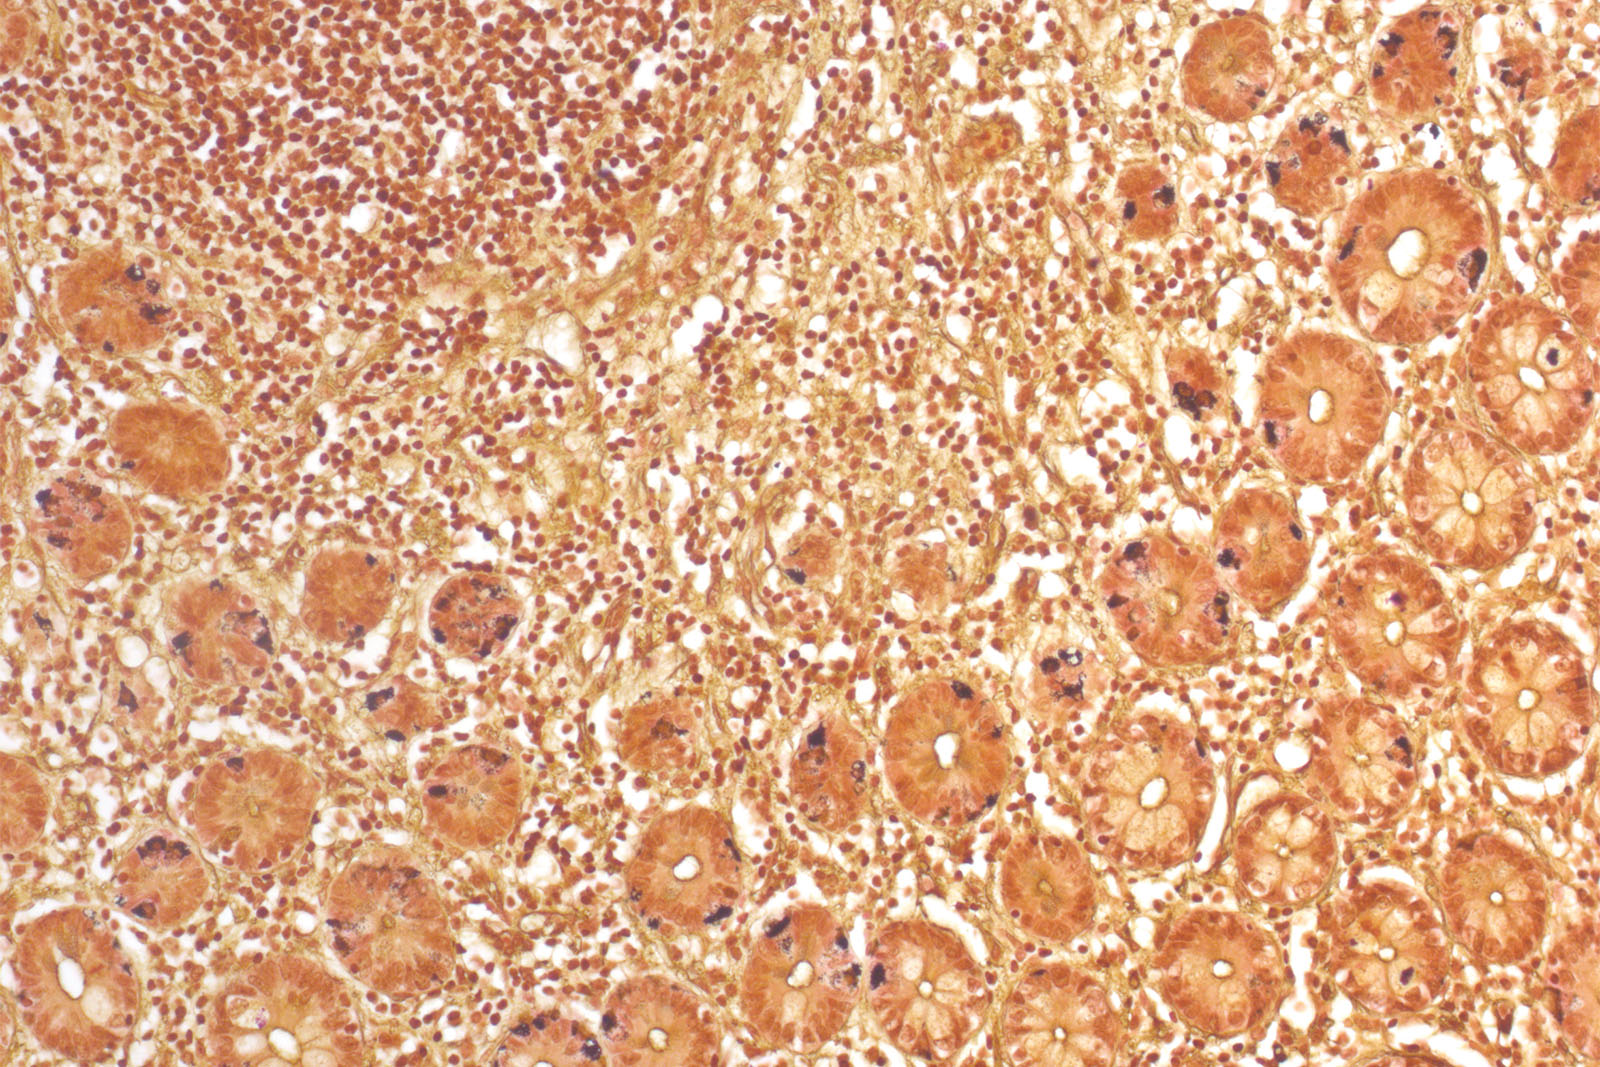

Grimelius kit is used in histology for visualization of argyrophilic structures in histology tissue sections. Certain tissues, such as neuroendocrine tumors can bind to silver ions from silver nitrate solution, but not reduce them to the visible form – elementary silver; this is why silver ion reduction during staining is achieved by exposing the section to the reducing hydroquinone solution and sodium sulfite. Excessive unbound silver ions are removed by rinsing the section with the sodium thiosulfate solution.